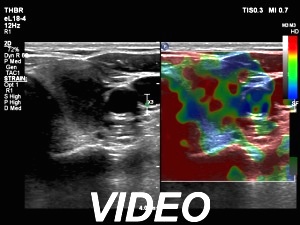

Ultrasonography. The thyroid was echonormal. There were two nodules in the right lobe. The upper was hyperechogenic-cystic while the lower was a minimally-moderately hypoechogenic. The latter had irregular, lobulated margins. There was a hypoechoic area in the upper two-third of left lobe. The discrete area presented ill-defined margins and decreased vascularization. A spongiform cyst was found in the lower pole of the left lobe.

Cytology of the nodule with irregular margins resulted in benign lesion, while cytology disclosed de Quervain's thyroiditis in the event of the hypoechoic area in the left lobe.